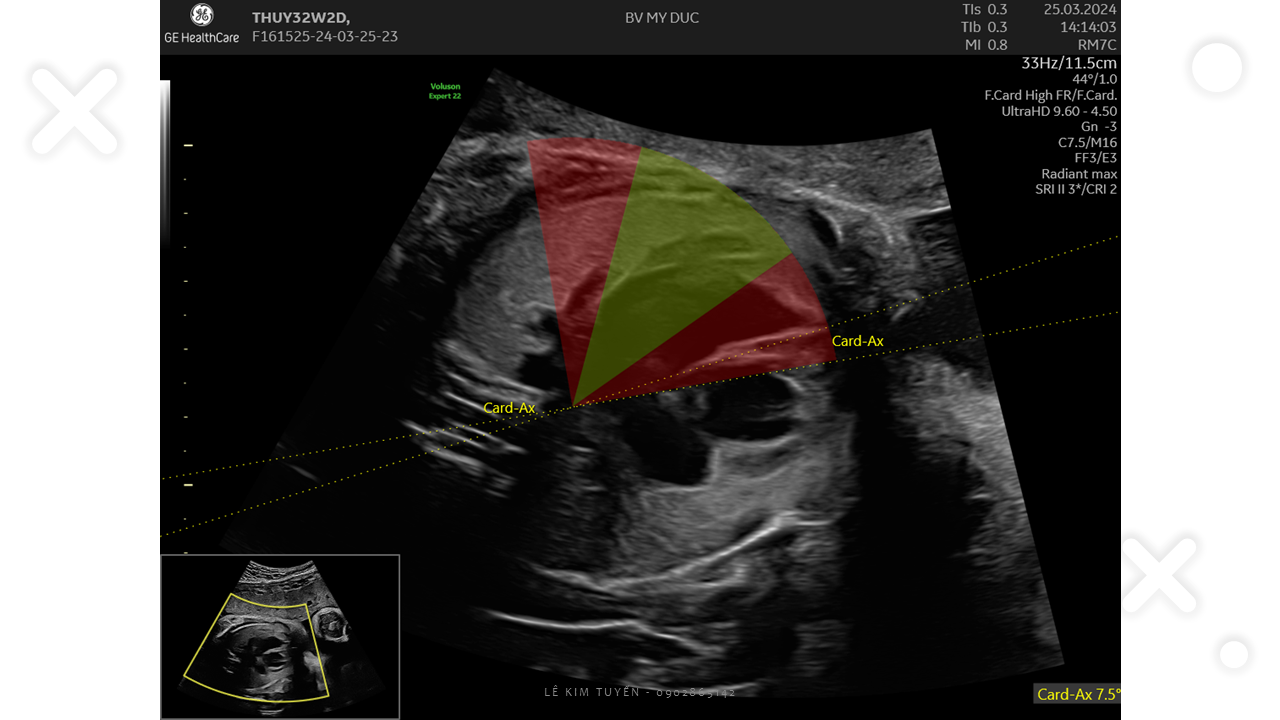

Siêu âm tim thai - Các kỹ thuật hiện đại

TS. BS. Lê Kim Tuyến

Bệnh viện Tim Tâm Đức